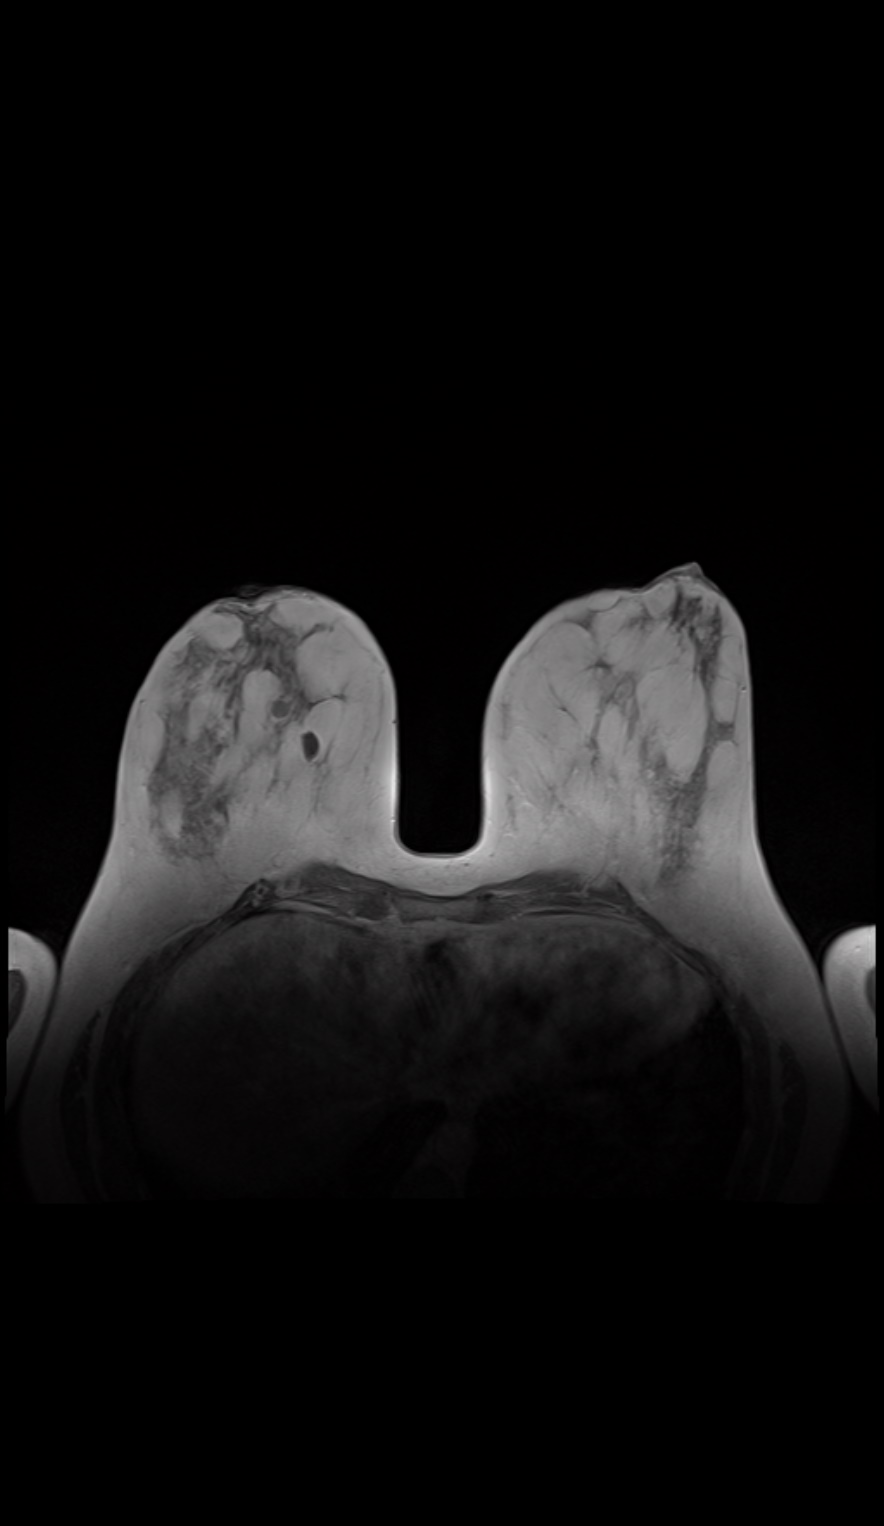

MRT-Brust